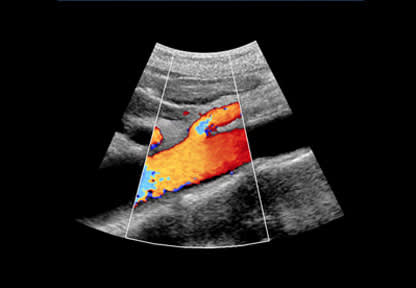

Abdominal Aortic Aneurysm Screening

Abdominal aortic aneurysm (AAA) screening is a way of detecting a dangerous swelling (aneurysm) of the aorta – the main blood vessel that runs from the heart, down through the abdomen to the rest of the body. This swelling is far more common in men aged over 65 than it is in women and younger men. An AAA usually causes no symptoms, but if it bursts, it’s extremely dangerous and usually fatal. Around 8 out of 10 people with a ruptured AAA either die before they reach hospital or don’t survive surgery. Screening involves a simple ultrasound scan of your stomach (abdomen), which takes about 10-15 minutes. If your abdominal aorta is not enlarged,…